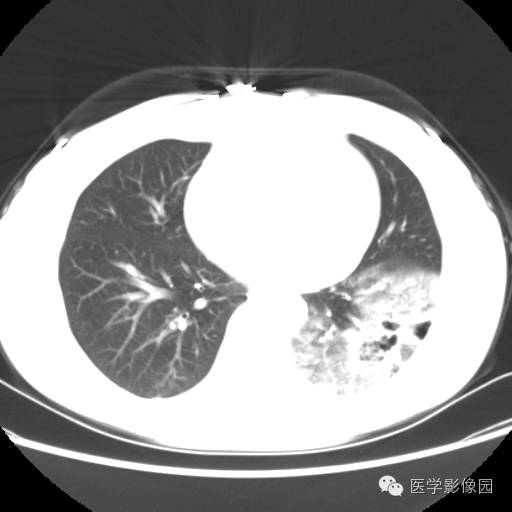

肺叶实变性支气管肺泡癌1例CT影像表现